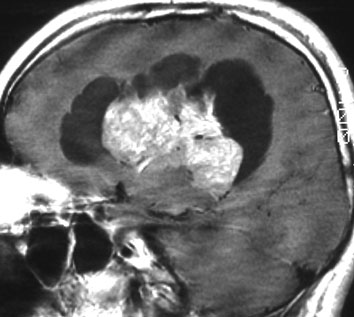

20代の男性の神経細胞腫です。側脳室の中のとても大きな腫瘍です。上段はガドリニウムという造影剤を入れた時のMRIです。下段の中央はCTですが,石灰化が見られます。脳外科の先生には,この脳室内腫瘍は一見transcallosal approach(経脳梁到達法)という手術で取れるように見えるかもしれませんが,そうではなくて,脳室の壁とくに上壁と側壁にくっついているのでなかなか取れません。この患者さんの場合は右の頭頂葉というところからtranscortical approach(経皮質到達法)で全摘出しました。後遺症もなく再発もなく術後10年が過ぎています。全部とれれば治ってしまう腫瘍です。